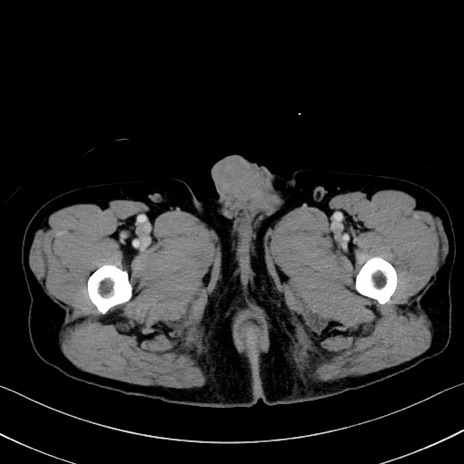

症例35(横断像)

【症例】70歳代 男性

【主訴】腹部膨満、嘔吐

【現病歴】昨日より腹部膨満感出現。本日増悪し、仙痛出現。嘔吐あり、受診。

【既往歴】糖尿病、胆摘後

【身体所見】BP 149/80mmHg、HR 74/min、BT 35.9℃、腹部:膨満、軟、圧痛なし。腸雑音減弱あり。上腹部正中切開瘢痕あり。

【データ】WBC 13500、CRP 1.72